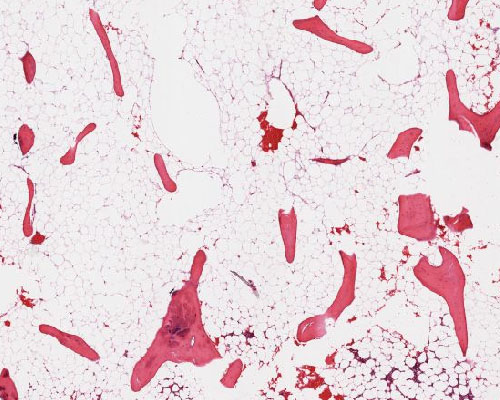

A78 Osteoporose

Schmale, deutlich ausgedünnte Trabekel, Fettmark.